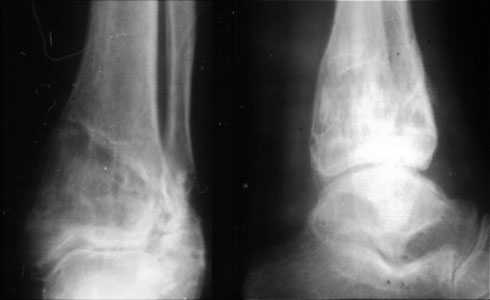

Аппаратом можно сделать все минимально инвазивно и травматично, вырастить клиновидный регенерат после чрескожной остеотомии через один или два разреза 0,5 см. В приложении похожий по локализации случай, только более давние последствия травмы с замыканием части зоны роста, деформация побольше, плюс укорочение голени было.

Уважаемый Александр то что вы показали это интересно, но это два разных случая. В ваших снимках большая деформация, которая требует выращивания массивного регенерата, поэтому здесь согласен лучше аппарат, а представленном случае дефект будет небольшой поэтому накостный синтез решит все проблемы за 2 недели без ключей 8*10 в течении 3-5 месяцев.Зачем себе создавать головную боль.

Согласен, тут деформация меньше, но все-таки заметная, почти 20 градусов. Я бы устранял ее как на приложенной картинке.